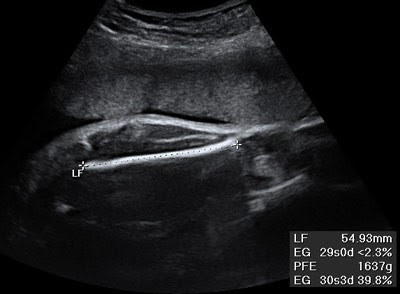

Ecografía

La energía usada es el ultrasonido que permite estudiar la impedancia acústica tisular. Es un método de bajo costo, no invasivo e inocuo. El transductor que se utiliza genera un haz de ultrasonido que rebota (eco) o pasa a través de las estructuras orgánicas según sus características tisulares. Los estudios se realizan "en tiempo real". El ultrasonido atraviesa con facilidad las estructuras líquidas y en menor grado los tejidos blandos y no atraviesa el aire ni el hueso.

Casi todas las colecciones líquidas se ven de color negro o anecogénicas, los tejidos blandos se presentan de color gris o hipoecogénicas, las que presentan ecogenicidad se llaman isoecogénicas y las que son más claras y brillantes se conocen como hiperecogénicas.

Las indicaciones para realizar una ecografía son:

1. Control de las caderas en el recién nacido (caderas luxables)

2. Lesiones traumáticas de las partes blandas (rupturas parciales o totales de ligamentos, músculo y tendones)

3. Control intraoperatorio de tumores del conducto raquídeo

4. Estudio de tumoraciones de partes blandas (diferencia masas sólidas de colecciones líquidas)

5. Guía parala biopsia percutánea de masas de partes blandas

6. Guía para el drenaje percutáneo de abscesos y otras colecciones líquidas de partes blandas

7. Control en la elongación de miembros

8. Diagnóstico intrauterino de malformaciones congénitas